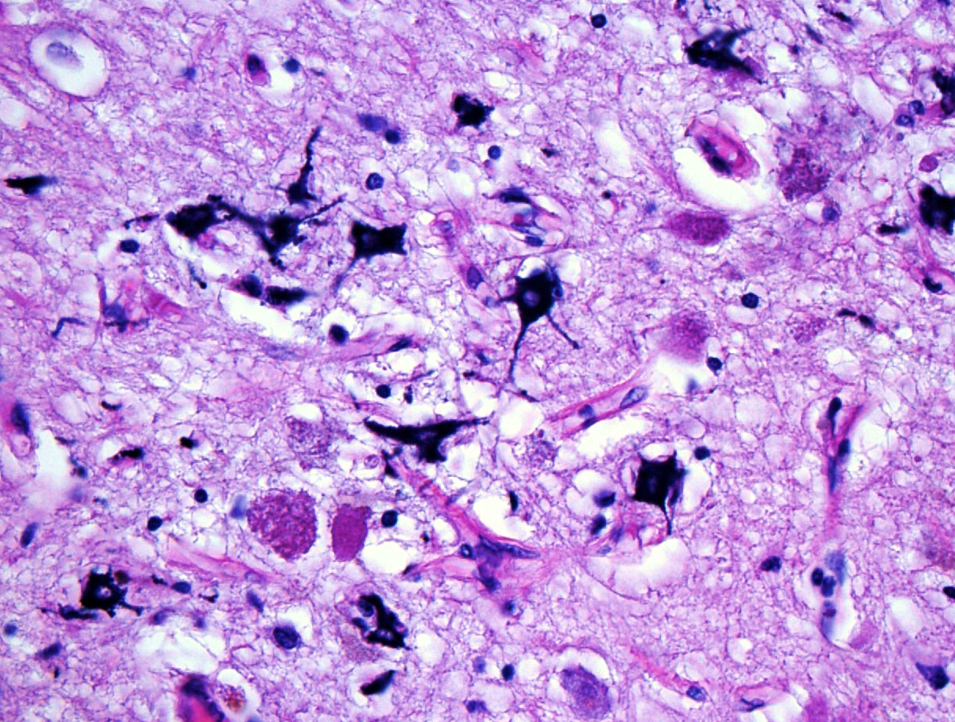

Microscopic (histologic) description

- Acute infarct (1 - 4 days) (Histopathology 2011;58:333)

- Neuronal changes: hypereosinophilic perikaryon (red dead neurons), cell body shrinkage, pyknosis (i.e., nuclear hyperchromasia), loss of demarcation of the nuclear features in later phases

- Neurons are more susceptible to ischemia than glia

- Neuropil vacuolation (i.e., tissue edema)

- May have some neutrophilic infiltrate

- Pannecrosis: all cell populations (i.e., neurons, glia, blood vessels) are necrotic; dead cells remain visible as hypereosinophilic structures that preserve the cell and nuclear outlines (pale neurons or "ghosts")

- Laminar necrosis

- Occurs due to variable susceptibility to hypoxia among the cortical histological layers

- In the mature brain, the most vulnerable neurons are located in cortical layers III, V, VI, Purkinje cells in the cerebellum and pyramidal cells of CA1 field in the hippocampus proper

- Geographic necrosis: liquefied necrotic tissue is well demarcated from the adjacent viable tissue

- Neuronal changes: hypereosinophilic perikaryon (red dead neurons), cell body shrinkage, pyknosis (i.e., nuclear hyperchromasia), loss of demarcation of the nuclear features in later phases

- Subacute (5 - 14 days)

- Dense macrophage infiltration and scattered siderophages

- Variable neutrophilic infiltration

- Peripheral reactive astrocytosis and microglial activation (i.e., rod shaped microglia)

- Hypereosinophilic neurons are still present in gray matter

- Neovascularization of necrotic tissue and reactive endothelial cells

- Axonal balloons can occur in all phases of ischemic injury (i.e., dilation of axons indicate injury with subsequent defective axonal transport)

- Neuronal ferrugination occurs occasionally in subacute to chronic infarcts, characterized by perykaryal mineralization (i.e., prominent basophilia)

Microscopic (histologic) images